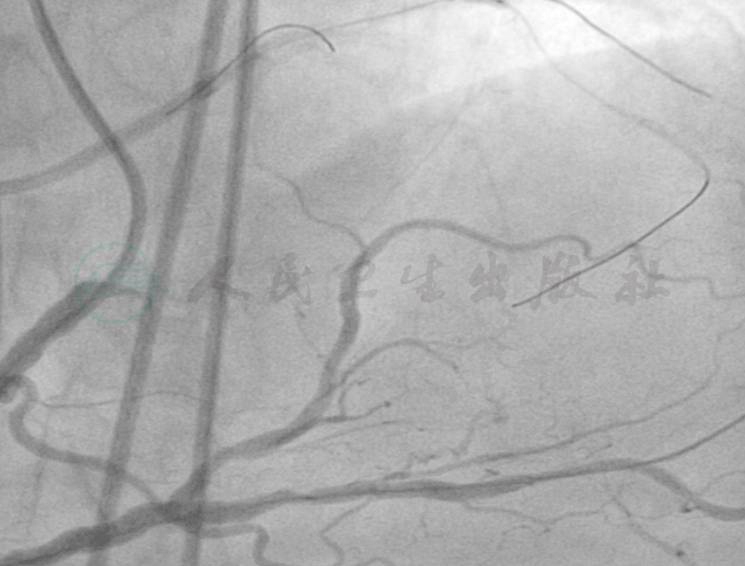

选用右桡动脉径路,6F血管鞘。造影发现:LAD近段齐头闭塞,无明确广残端;LCX中段闭塞;LM、中间支血管通畅,血流TIMI 3级;RCA近段70%~80%狭窄,RCA中远段70%~80%狭窄,血流TIMI 3级,见丰富的右-左侧支循环(图1~图4)。

一个月后行左冠PCI。考虑到LCX为中段闭塞,开通可能性大,因此先尝试开通LCX,并且考虑到RCA经间隔支对LAD和LCX提供了良好的侧支循环,遂采用前向结合逆向技术。选用右侧及左侧股动脉途径,保证足够的支撑力。右冠选择6F AL1.0指引导管,左冠选择6F EBU 3.5指引导管,选用Asahi Sion导丝在Asahi Corsair导管支持下经RCA远段侧支循环将导丝进入LCX侧支血管,但未能够进入LCX远段(图5),换用Runthrough NS导丝进入微导管成功进入LCX-OM远段,但不能通过LCX闭塞段,改用Pilot 50导丝后进入假腔(图6)。改正向技术,左冠在Finecross微导管支持下,用Pitlot 50成功通过LCX近中段闭塞病变处进入LCX远段(图7),以GOODMAN 1.3mm×10mm和2.0mm×15mm球囊预扩张LCX远段到近段病变(图8),发现LCX中段病变处出现造影剂渗漏,遂用2.0mm×15mm球囊以5atm压迫造影剂渗漏处约30分钟(图9、图10)。

图5 左冠选择6F EBU3.5指引导管,选用ASAHI Sion导丝在ASIHI Corsair导管支持下经RCA远段侧支循环将导丝进入LCX侧支血管,但未能够进入LCX远段